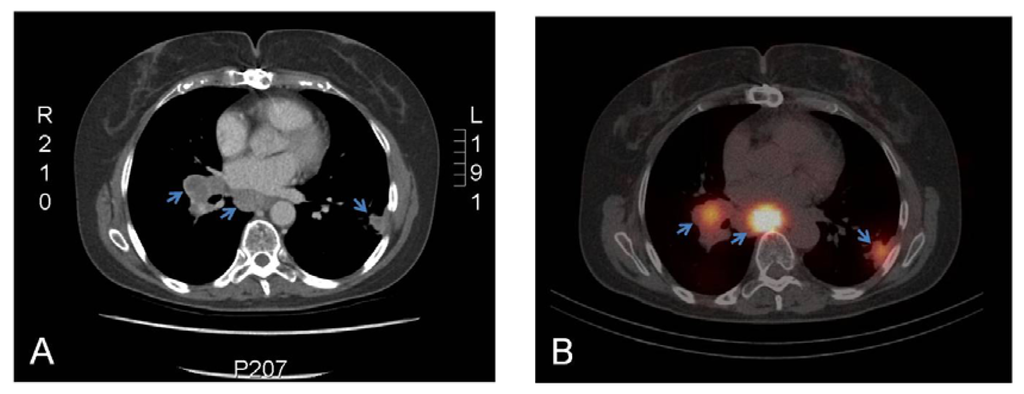

- Divgi, C.R.; Pandit-Taskar, N.; Jungbluth, A.A.; Reuter, V.E.; Gonen, M.; Ruan, S.; Pierre, C.; Nagel, A.; Pryma, D.A.; Humm, J.; et al. Preoperative characterisation of clear-cell renal carcinoma using iodine-124-labelled antibody chimeric g250 (124I-cg250) and pet in patients with renal masses: A phase i trial. Lancet Oncol 2007, 8, 304–310. [Google Scholar]

- Divgi, C.R.; Uzzo, R.G.; Gatsonis, C.; Bartz, R.; Treutner, S.; Yu, J.Q.; Chen, D.; Carrasquillo, J.A.; Larson, S.; Bevan, P.; et al. Positron emission tomography/computed tomography identification of clear cell renal cell carcinoma: Results from the redect trial. J. Clin. Oncol 2013, 31, 187–194. [Google Scholar]

| Divgi et al. [34] | 2007 | 124I-cG250 | 26 | Primary RCC | 15/16 ccRCC imaged | Prospective cG250-immunoPET |

| Divgi et al. [35] | 2013 | 124I-cG250 | 226 | Primary RCC | 124/143 ccRCC imaged (sens. & spec. 86%) | Phase III, REDECT trial |

| Muselaers et al. [36] | 2013 | 111In-cG250 | 29 | Primary RCC | 15/16 ccRCC imaged | 111In-cG250 immunoSPECT |